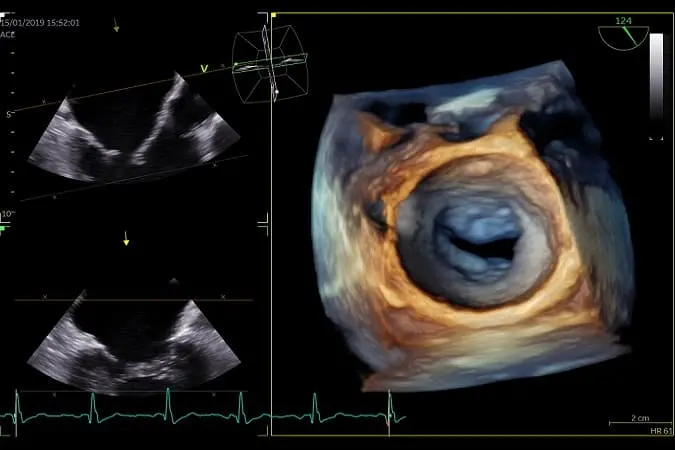

Τρισδιάστατη ηχωκαρδιογραφία (3D/4D Echo)

Η τρισδιάστατη ηχωκαρδιογραφία είναι η πιο σημαντική εξέλιξη των ημερών μας στην ηχωκαρδιολογία.

Με τη μέθοδο αυτή υπάρχει η δυνατότητα να διαγνώσουμε βαλβιδοπάθειες, όπως η πρόπτωση μιτροειδούς βαλβίδος και να απεικονίσουμε την καρδιακή δομή που θέλουμε ακριβώς όπως θα την έβλεπε ένας καρδιοχειρουργός σε χειρουργείο ανοιχτής καρδιάς.

Το 3D echo επίσης μπορεί με σχεδόν 100% αξιοπιστία να αξιολογήσει το μέγεθος και τη λειτουργικότητα της καρδιάς φτάνοντας στα επίπεδα αξιοπιστίας της μαγνητικής καρδιάς. Στα μεγάλα εργαστήρια του εξωτερικού και σε ορισμένα στην Ελλάδα όπως και στο δικό μας είναι απαραίτητη η τρισδιάσταση εκτίμηση των βαλβίδων και των περιστατικών καρδιακής ανεπάρκειας, προκειμένου να προχωρήσουμε στη σωστή θεραπεία για τον ασθενή μας.